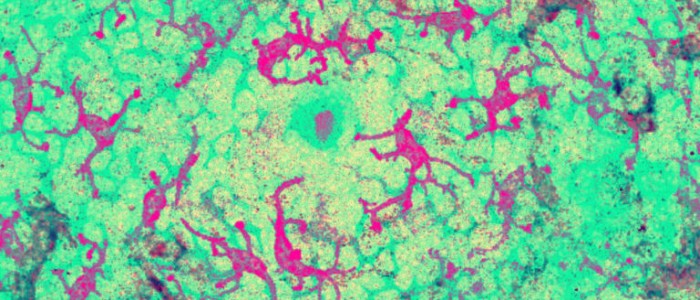

При лікуванні використовуються Т-клітини, тип білих кров'яних клітин, які допомагають імунній системі нашого організму шляхом сканування і знищення аномальних клітин. Для довідки, вчені недавно почали використовувати цю здатність у боротьбі з раком за допомогою терапії під назвою CAR-T, яка включає видалення Т-клітин з крові пацієнта і генетичну інженерію їх для пошуку і знищення ракових клітин.

Ця молекула з'являється на поверхні багатьох типів ракових клітин, а також здорових клітин, але відомо, що Т-клітини, оснащені цим TCR, вбивають тільки ракові клітини.

І не тільки вид, пов'язаний з одним типом раку. Коли дослідники з Кардіффа оснастили Т-клітини в лабораторних тестах цим новим TCR, клітини вбили клітини легенів, шкіри, крові, товстої кишки, молочної залози, кісток, передміхурової залози, яєчників, нирок і шийки матки — при цьому ігноруючи здорові клітини.